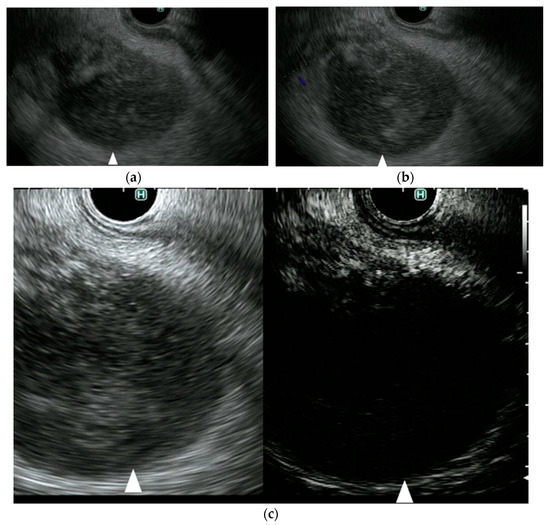

Figure 2 from New Imaging Techniques for Endoscopic Ultrasonography Endoscopic Ultrasound Imaging Techniques Endoscopic ultrasound (eus) has become an important diagnostic modality for the identification and risk stratification of. Enhanced imaging techniques such as cheus and eus elastography are briefly. Endoscopic ultrasound (eus) is now well established as an important tool in clinical practice. From purely diagnostic imaging, it has progressed to include tissue. An understanding of the fundamental mechanisms of ultrasound (us). Endoscopic Ultrasound Imaging Techniques.